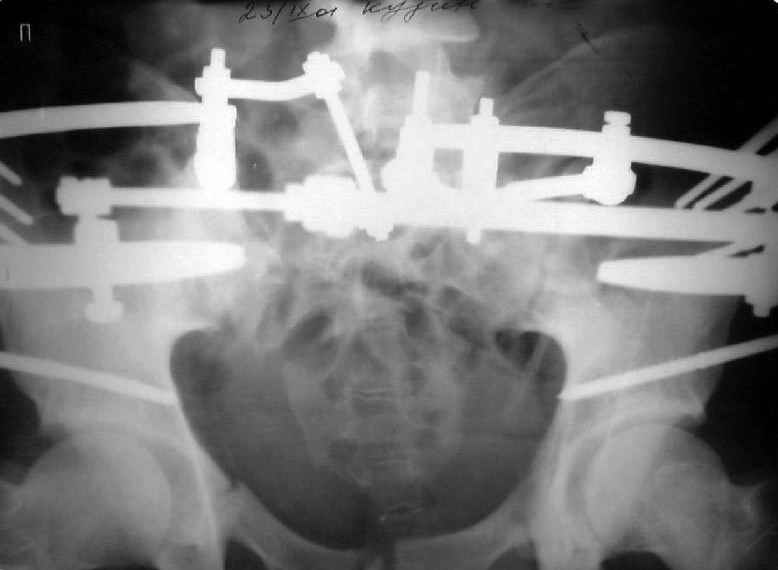

Уважаемые коллеги! Хотел-бы обсудить варианты лечения больной с застарелым переломом таза. Возраст 40 лет. Травма 11 месяцев назад. Главный травматолог Камчатского Военно-морского госпиталя Юрий Алексеевич Булахтин

У больного судя по всему вертикальная деформация таза. А каковы основные жалобы пациента и какие у него функциональные требования?

Мы, как правило, в подобных случаях проводим оперативное лечение в несколько этапов. Первым устраняем деформацию при помощи АВФ (кольцевой конструкции с фиксацией задних отделов), вторым- выполняем введение илиосакралых винтов, накостный остеосинтез передних отделов.

Для информации к размышлению о возможности исправления имеющейся деформации предлагаю похожий случай.